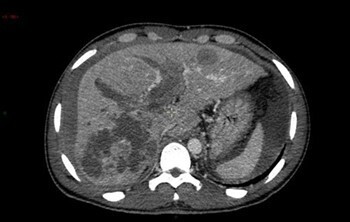

Question 4 - Vous constatez (une ou plusieurs réponses exactes) :

Non pas du foie gauche (= lobe gauche + segment IV) mais du lobe gauche (segments II et III).

La dysmorphie hépatique est caractérisée par une hypertrophie de segment I (en arrière du tronc porte et en avant de la veine cave inférieure) et du lobe gauche (segments II et III situés à gauche de la veine hépatique gauche) ; ainsi que par une hypotrophie du segment IV (situé entre les veines hépatiques gauche et médiane, séparé du lobe gauche par le plan passant par la veine hépatique gauche et le ligament rond). Peut également s’y associer une hypotrophie du secteur postérieur du lobe droit (segments VI et VII).

Pour la segmentation hépatique, voir la figure ci-dessous : On retrouve comme autre signe d’hépatopathie chronique les contours bosselés.

Les signes d’hypertension portale visibles en scanner sont :

– les voies veineuses de dérivation porto-systémiques (spléno-rénales, gastro-rénales, mésentériques, rétro-péritonéales…) ;

– la splénomégalie.